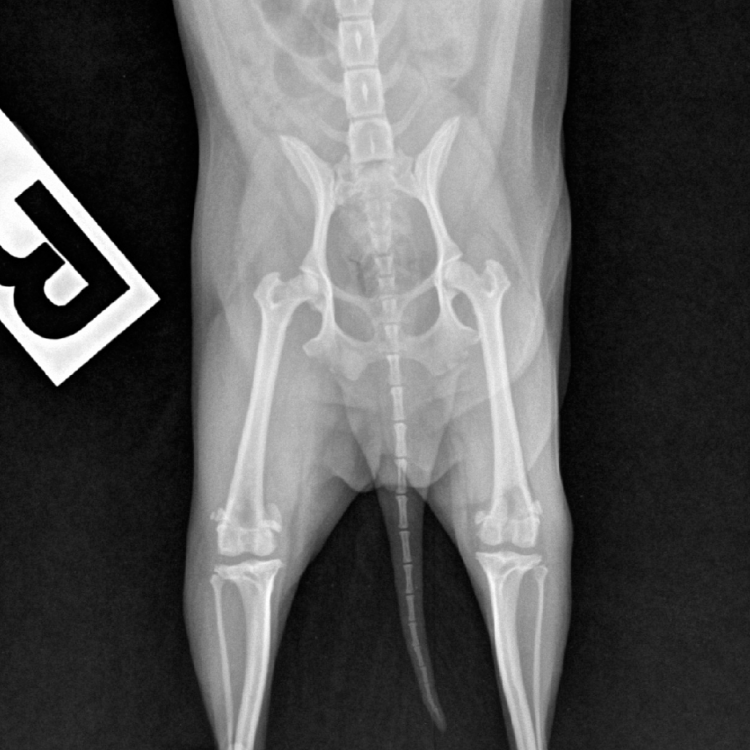

การตรวจเอกซ์เรย์ (X-Ray) เป็นการตรวจวินิจฉัยด้วยรังสี x โดยภาพที่ได้จะมีสีขาว - ดำ

ที่มีระดับความเข้มของสีที่แตกต่างกันขึ้นกับการดูดกลืนรังสีของแต่ละอวัยวะ

ตำแหน่งในการเอ็กเรย์ถูกแบ่งออกเป็น 3 ระบบหลักๆ คือ

นอกจากนั้นในกรณีที่ต้องการถ่ายภาพเอกซเรย์ (X-ray) ด้วย เทคนิคพิเศษโดยการกินสารทึบรังสีเพื่อตรวจวินิจฉัยความผิดปกติของระบบทางเดินอาหาร ไม่ว่าจะเป็นทางเดินอาหารส่วนต้นหรือส่วนปลาย ควรที่จะเตรียมตัวสัตว์โดยการงดน้ำ และอาหาร เพื่อลดปริมาณกากอาหารที่อาจไปขัดขวางทางผ่านของสารทึบรังสีที่ให้